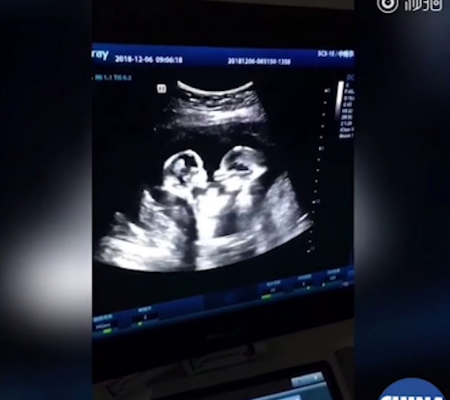

Vídeo: Gêmeas são vistas “lutando” no útero da mãe em ultrassom

O exame mostrou as gêmeas chinesas Cherry e Stranwberry protagonizando uma “luta” bastante fofa dentro do útero da mãe. Um vídeo do exato momento foi divulgado pelo pai das bebês, Tao. Em pouquíssimo tempo a publicação viralizou com internautas de todo o mundo amando ver as cenas das gêmeas brigonas.

Embora a gravidez tenha sido de risco, com as duas irmãs compartilhando o mesmo saco amniótico e a placenta, ambas nasceram no dia 8 de abril. O parto foi realizado em uma cesareana de emergência, mas as duas meninas passam bem. A mais velha delas nasceu com 1,95 kg, enquanto a menor pesava 1,62 kg, segundo o Yangzhou Evening News.